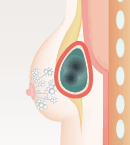

多くの場合、ヒアルロン酸を注入すると体は異物が入ってきたと捉えるので、コラーゲン線維の被膜で閉じ込めようとします。しかし、これは正常な生体反応。通常なら、被膜の薄いうちに体内の酵素成分がヒアルロン酸を分解、吸収されてなくなります。しかし、何らかの理由で分解されるより前に厚い被膜ができてしまった場合、しこりとして残ってしまうのです。

- しこりになる場合

- ヒアルロン酸の周囲に

被膜を形成

- 分解・吸収されることなく残留